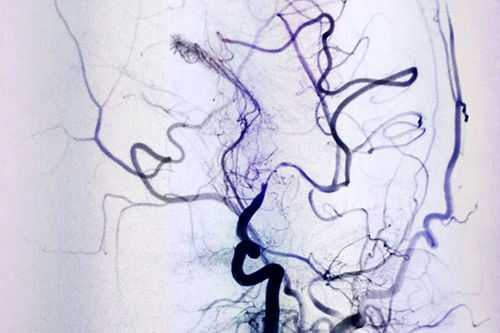

DSA血管介入诊断和治疗,像一种“血管艺术”,初看如水墨丹青一样的术中影像图,如同医护人员用智慧和技巧绘制的生命图谱。上海蓝十字脑科医院DSA血管介入诊疗是医院特色科室,拥有非常完善和先进的设备,李振并主任已经使用DSA成功诊断和治疗了很多大面积脑梗患者。

DSA血管造影,仿佛医生绘出的生命图腾

术前DSA影像显示,患者大脑中动脉血管70%以上狭窄